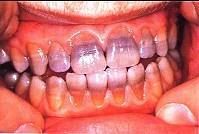

问题 关于四环素牙,下列哪—项错误 ( )

选项 A.四环素牙的着色是永久的 B.四环素在牙本质中的沉积比在釉质中高4倍 C.四环素可通过胎盘引起乳牙着色 D.四环素对牙的影响仅仅是着色,影响美观 E.通常前牙比后牙着色深

答案 D